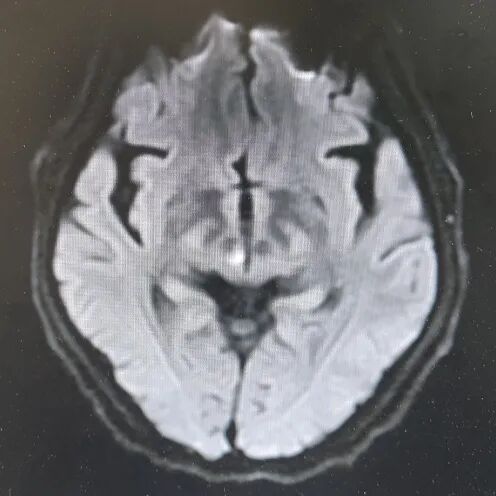

引言 生活中,很多人会突然出现“看东西重影”的情况,往往以为是眼睛疲劳或近视加深,并没有太当回事。然而,这背后可能隐藏着甲亢、脑梗、重症肌无力甚至肿瘤等十余种疾病的信号,是一个需要警惕的“隐形杀手”。 面对这类病因错综复杂的“复视”患者,市二院神经内二科赵智江主任带领团队,凭借丰富的临床经验和深厚的神经疾病诊疗功底,抽丝剥茧,多次成功揪出导致视物成双的“真凶”,为患者赢得了宝贵的治疗时机。 Part.01 复视背后,病因五花八门 神经内二科团队诊治了多位以“视物成双”为主诉的患者,其最终病因各异,充分体现了神经科疾病“同症异源”的复杂性。 以为是眼病,其实是甲亢 患者因复视就诊,经查双眼突出,影像检查发现控制眼球的肌肉异常肥厚。结合甲状腺功能检查,最终确诊为“甲亢性眼肌病”,其原因在甲状腺功能亢进的眼部表现。后经针对性纠正甲状腺功能,患者复视症状显著改善,眼外肌肥厚得到有效控制。 眼眶核磁 甲功结果 眼球状态 复视眼痛,原是痛性眼肌麻痹 患者右眼不仅看东西重影,还出现上睑下垂、眼痛等症状。团队排除其他可能后,诊断为痛性眼肌麻痹(Toloas-Hunt综合征),这是一种自身免疫性炎症。经治疗,患者眼睑下垂症状减轻,眼痛及复视基本消失,眼球运动范围显著恢复。 梅毒隐匿,损伤颅神经 患者因眼皮抬不起、眼球转动不灵并视物重影入院。常规血清检查发现梅毒抗体阳性,排除其它原因导致的复视,最终明确为“神经梅毒”侵蚀颅神经所致。确诊后立即给予驱梅治疗,效果明显,眼皮能抬起来了,重影消失了,眼球转动也灵活了。 糖尿病悄悄损伤神经 两位糖尿病患者,均以突发复视就诊。团队精准判断,发现分别是高血糖损伤了“动眼神经”和“外展神经”,属于糖尿病性单神经病变,表现为不同类型的复影(上下重影或水平重影)。明确诊断后,经严格控糖,辅以营养神经药物等综合对症治疗,患者病情好转,顺利出院。 脑梗“瞄准”不同区域 三位患者均因复视就诊,但伴随症状各异,有的行走不稳,有的走路右偏。赵智江主任团队通过精细的神经系统查体,精准定位于中脑的动眼神经核、桥脑的内侧纵束等。不同脑区梗死,复视的表现也完全不同。后通过溶栓药物、抗血小板药物、改善循环治疗等针对性治疗,辅以康复治疗,患者身体逐渐好转,出院时已无视物成双症状。 三位患者的核磁 典型信号——晨轻暮重 患者出现复视,伴言语不利、吞咽困难、饮水呛咳等症状。其中复视有个鲜明特点——早晨轻、傍晚重,疲劳后加重。经专项检查,确诊为“重症肌无力”(眼肌型)。这是一种神经肌肉接头疾病,免疫调节治疗可有效控制。经过一段时间的治疗,患者复视症状明显缓解,言语不清、吞咽困难症状得到显著改善。治疗前患者只能进食流食,治疗后可自主进食固体食物。 肿瘤病史者,需警惕转移 淋巴瘤患者在化疗期间出现复视和面瘫。团队通过脑脊液等深入检查,排除感染等因素,最终诊断为脑膜癌病。 嗜睡头晕,病因在营养 患者急性起病,表现为复视、头晕、嗜睡、走路不稳。团队结合其既往史和典型眼球活动障碍,迅速锁定病因——因维生素B1严重缺乏导致的“韦尼克脑病(Wernicke)”。补充维生素B1一周以后,患者复视症状改善、走路平稳、神志清楚,可独立行走。 Part.02 精准诊疗,揪出“元凶”是关键 赵智江主任指出:“复视只是一个临床症状,其背后可能是内分泌、炎症、代谢、脑血管、自身免疫、肿瘤等多种病因在神经系统上的投射,涉及学科广泛。” 市二院神经内二科团队通过详细追溯病史、进行一丝不苟的神经系统专科查体(尤其是眼球运动检查),初步判断病变可能位于动眼、滑车、外展神经的神经核团,神经及其所支配的肌肉、神经-肌肉接头等部位,然后精准选择并解读影像学、免疫学、生化及脑脊液等检查结果,最终整合信息,明确诊断,为患者制定出针对性的治疗方案。 市二院神经内二科在赵智江主任的带领下,始终致力于复杂疑难神经系统疾病的诊疗攻坚。科室凭借严谨的临床路径、对神经解剖与病理生理机制的深刻把握,以及精湛的诊疗技术,为众多罕见病与危重患者精准定位病因、制定个体化治疗方案,有效提升了救治成功率与患者长期生活质量。 提醒市民:如果突然出现视物重影,尤其是伴有眼皮下垂、眼球转动不灵、疼痛、头晕、行走不稳或其他神经系统症状时,切勿掉以轻心,应及时重视,这些症状有时可能与神经系统疾病相关。为了明确原因,获得更全面的评估,您可以考虑到神经内二科就诊,由专业医生进一步检查与诊断,以便尽早获得适合的照顾与治疗。 Part.03 人民医院 人民名医 赵智江 主任医师 副教授 ·葫芦岛市第二人民医院神经内二科主任 ·中国卒中学会高级会员 ·中国老年保健医学研究会老年脑血管病分会委员 ·北京神经内科学会脑小血管病学会委员 ·安徽医药杂志审稿专家 ·辽西神经疾病专科联盟理事 ·辽西认知功能障碍联盟理事 ·辽西神经免疫学会委员 ·葫芦岛市医学会神经病学分会委员 专业特色:以脑血管病为核心研究方向,擅长各类神经系统疾病的诊疗,尤其在脑血管病、帕金森综合征、头晕、头痛、癫痫、重症肌无力、多发性硬化等神经免疫性疾病以及其它神经系统疑难、危重疾病的诊疗方面积累了丰富的临床经验。 出诊时间:每周一、周四全天 咨询热线:0429-8010317